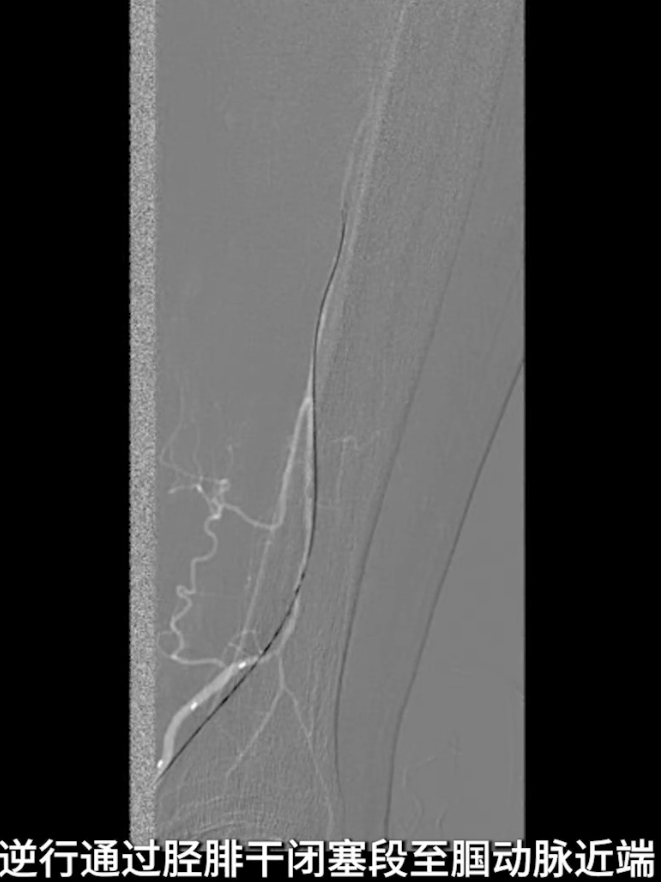

逆穿技术应用:改为逆穿胫后动脉远端,支撑导管配合V18导丝经交通支逆行进入腓动脉远端,逐步推送导丝导管通过胫腓干闭塞段,直至腘动脉近端真腔,与近端导管完成对接,建立膝下流出道操作轨道。